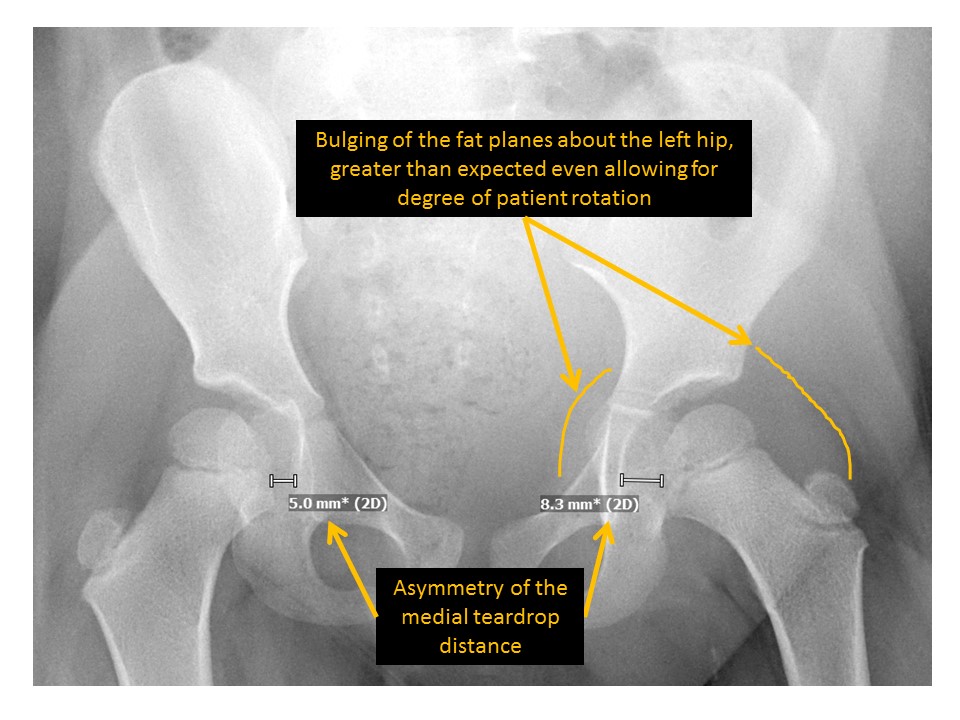

The teardrop distance is asymmetric. [Yes/No]

There is bulging of the fat planes about the hips. [Yes/No]